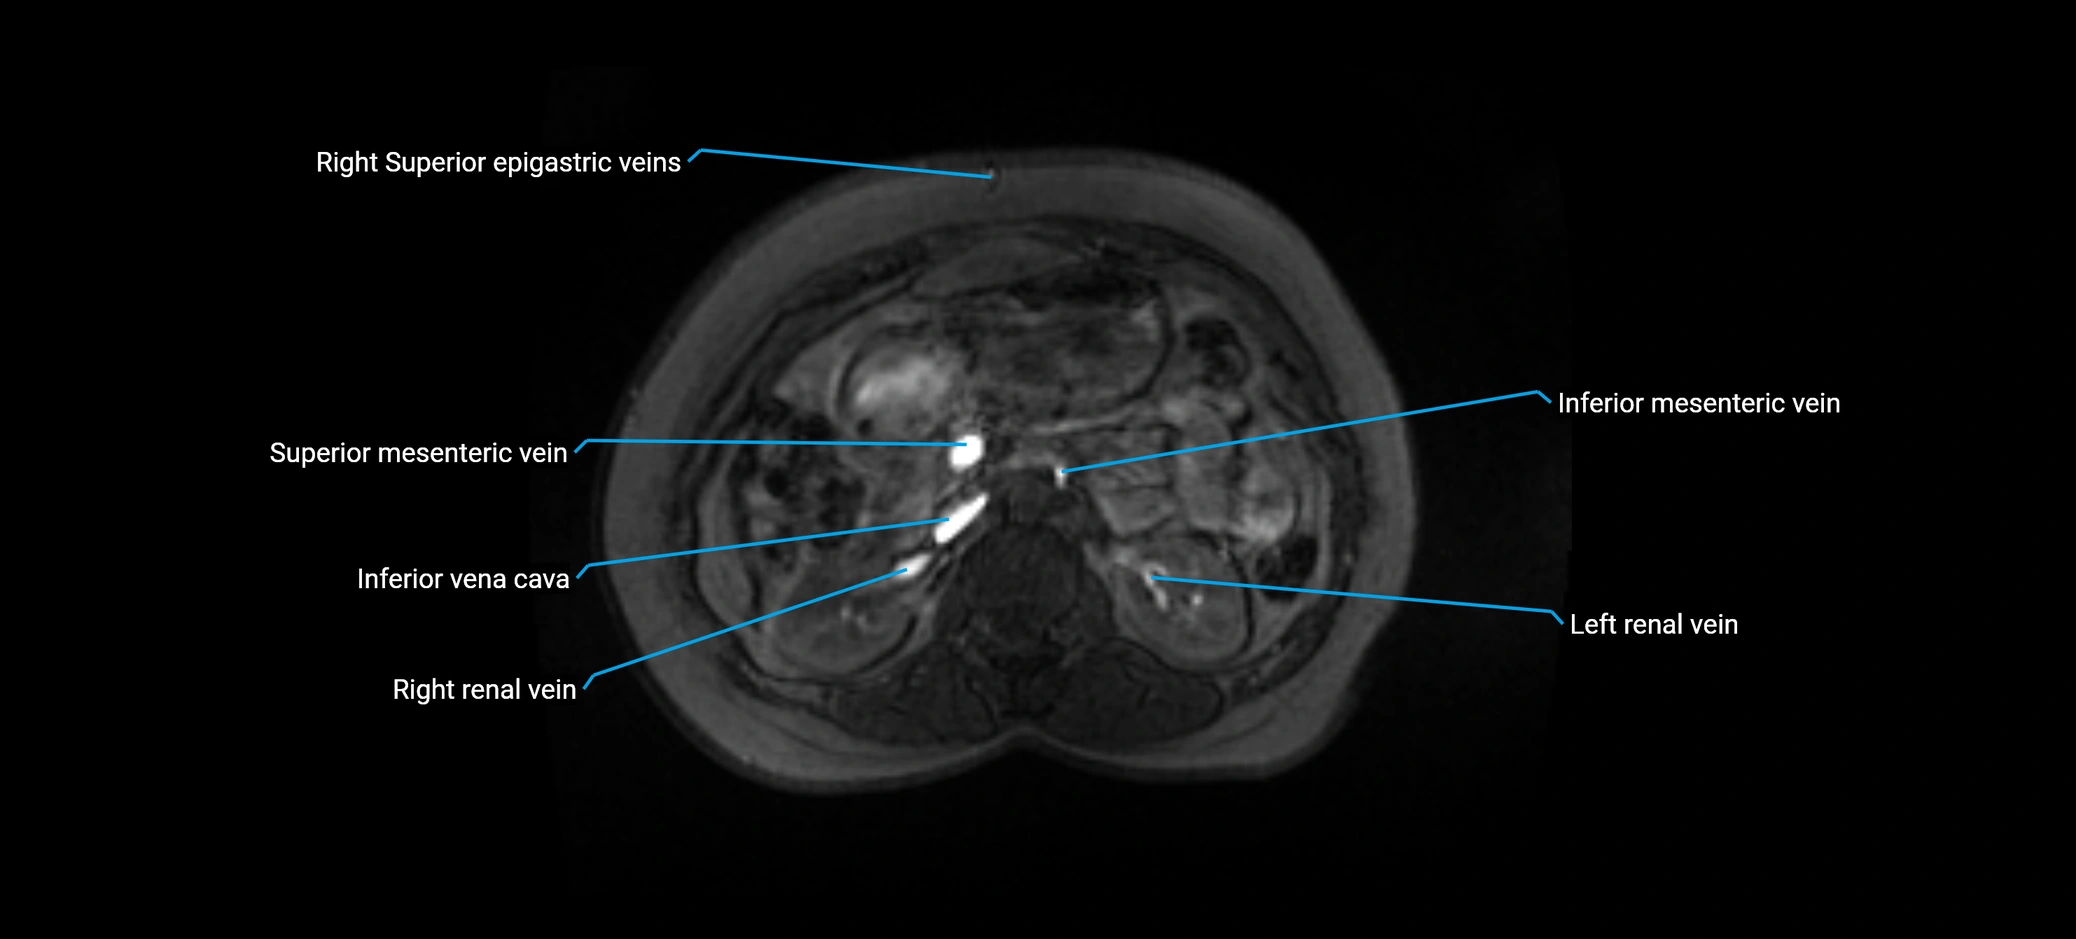

image